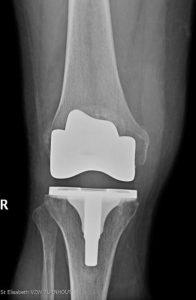

Het afgesleten kraakbeen zal tijdens deze open ingreep vervangen worden door kunstcomponenten.

Bij het plaatsen van een totale knieprothese worden deze oppervlakken opnieuw bekleed (met metaal en plastiek). Deze materialen glijden bijna even goed als kraakbeen en zijn zeer slijtvast. De materialen zijn zo gekozen dat het lichaam ze goed verdraagt (en er dus geen afstotingsverschijnselen optreden).

Met de huidige techniek gaat deze prothese in 95% van de gevallen mee voor meer dan 20 jaar.